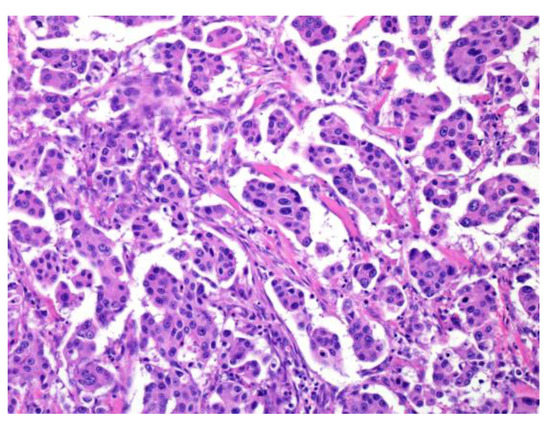

AdCC consists of two main cell types: ductal cells located in the inner part and myoepithelial cells located in the outer part of the duct. The ductal cells have eosinophilic cytoplasm and uniformly round nuclei, while the myoepithelial cells have a clear cytoplasm and hyperchromatic angular nuclei [2,44] (Bishop, J.A. et al. pp. 337–356). Perineural invasion is an AdCC hallmark, and genetically, it is characterized by MYB or related gene translocations. Typically, AdCC comprises pseudocysts and true glandular lumina. AdCC shows three growth patterns: tubular, cribriform, and solid [2,44] (Bishop, J.A. et al. pp. 337–356). Consequently, the following histological grading is used for its classification: tubular predominant as grade Ⅰ, cribriform predominant as grade Ⅱ, and solid predominant as grade Ⅲ (Figure 5) [2,44,45].

Figure 5.

The histological grade of adenoid cystic carcinoma (AdCC). The tumor shows tubular (left), cribriform (middle), and solid (right) growth patterns.

Although AdCCs with >30% solid components have been shown to be more aggressive, any solid tumor component may be a high-grade tumor, as described in the minAmax system [46,47,48]. Necrosis, marked pleomorphism, or high levels of mitoses are only seen in the solid pattern and are not utilized in the grading system [2] (pp. 337–356).